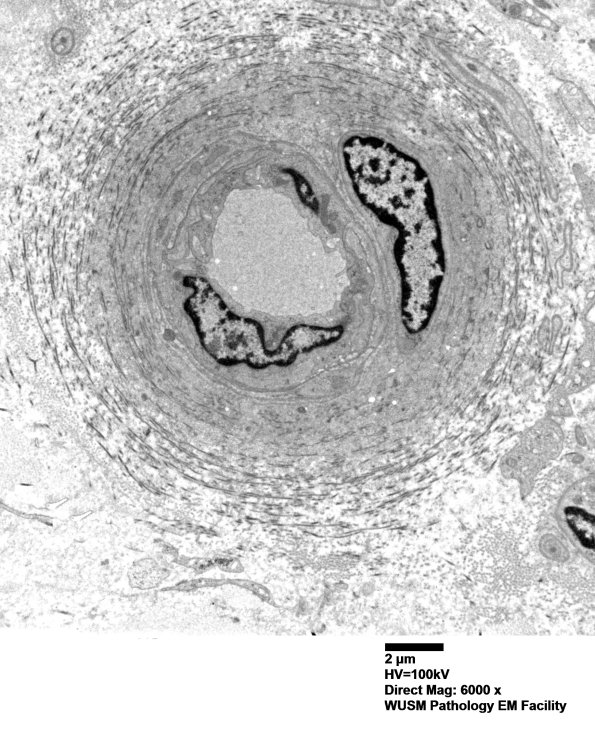

17B1-3 The vessels are mildly enlarged by basal lamina and collagen. (electron micrographs)